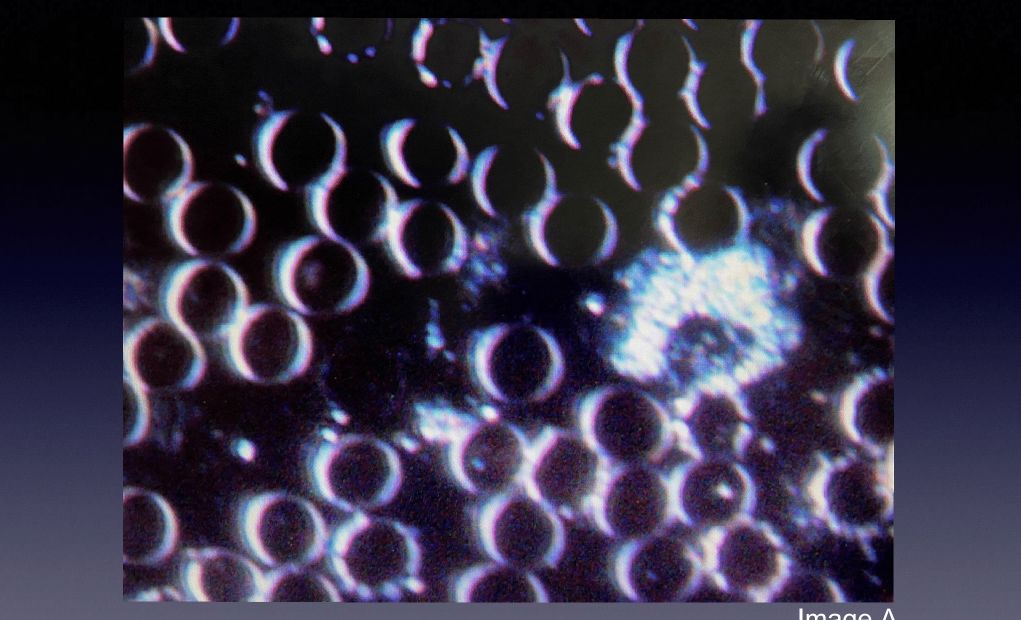

Pre-Metadichol

These images show Roman’s blood sample before taking Metadichol through NANO SOMA® Liquid. His blood cells appear healthy, round, and well-spaced.

In this result, however, the Epstein Barr Virus (EBV) was present. This is seen in the small white dots inside the cells. Cell clumping is common where there is an EBV infection.